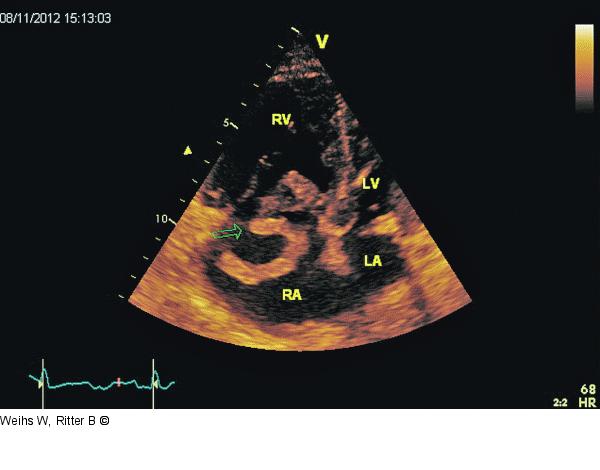

Abbildung 4: Vierkammerblick Modifizierter apikaler Vierkammerblick. Flottierender Thrombus (Pfeil) im RA mit Prolabieren in den RV. Hypokinesie des rechten Ventrikels mit Ausnahme des Apex („McConell“-Zeichen). RV: rechter Ventrikel; LV: linker Ventrikel; RA: rechter Vorhof; LA: linker Vorhof. |

Modifizierter apikaler Vierkammerblick. Flottierender Thrombus (Pfeil) im RA mit Prolabieren in den RV. Hypokinesie des rechten Ventrikels mit Ausnahme des Apex („McConell“-Zeichen). RV: rechter Ventrikel; LV: linker Ventrikel; RA: rechter Vorhof; LA: linker Vorhof. |